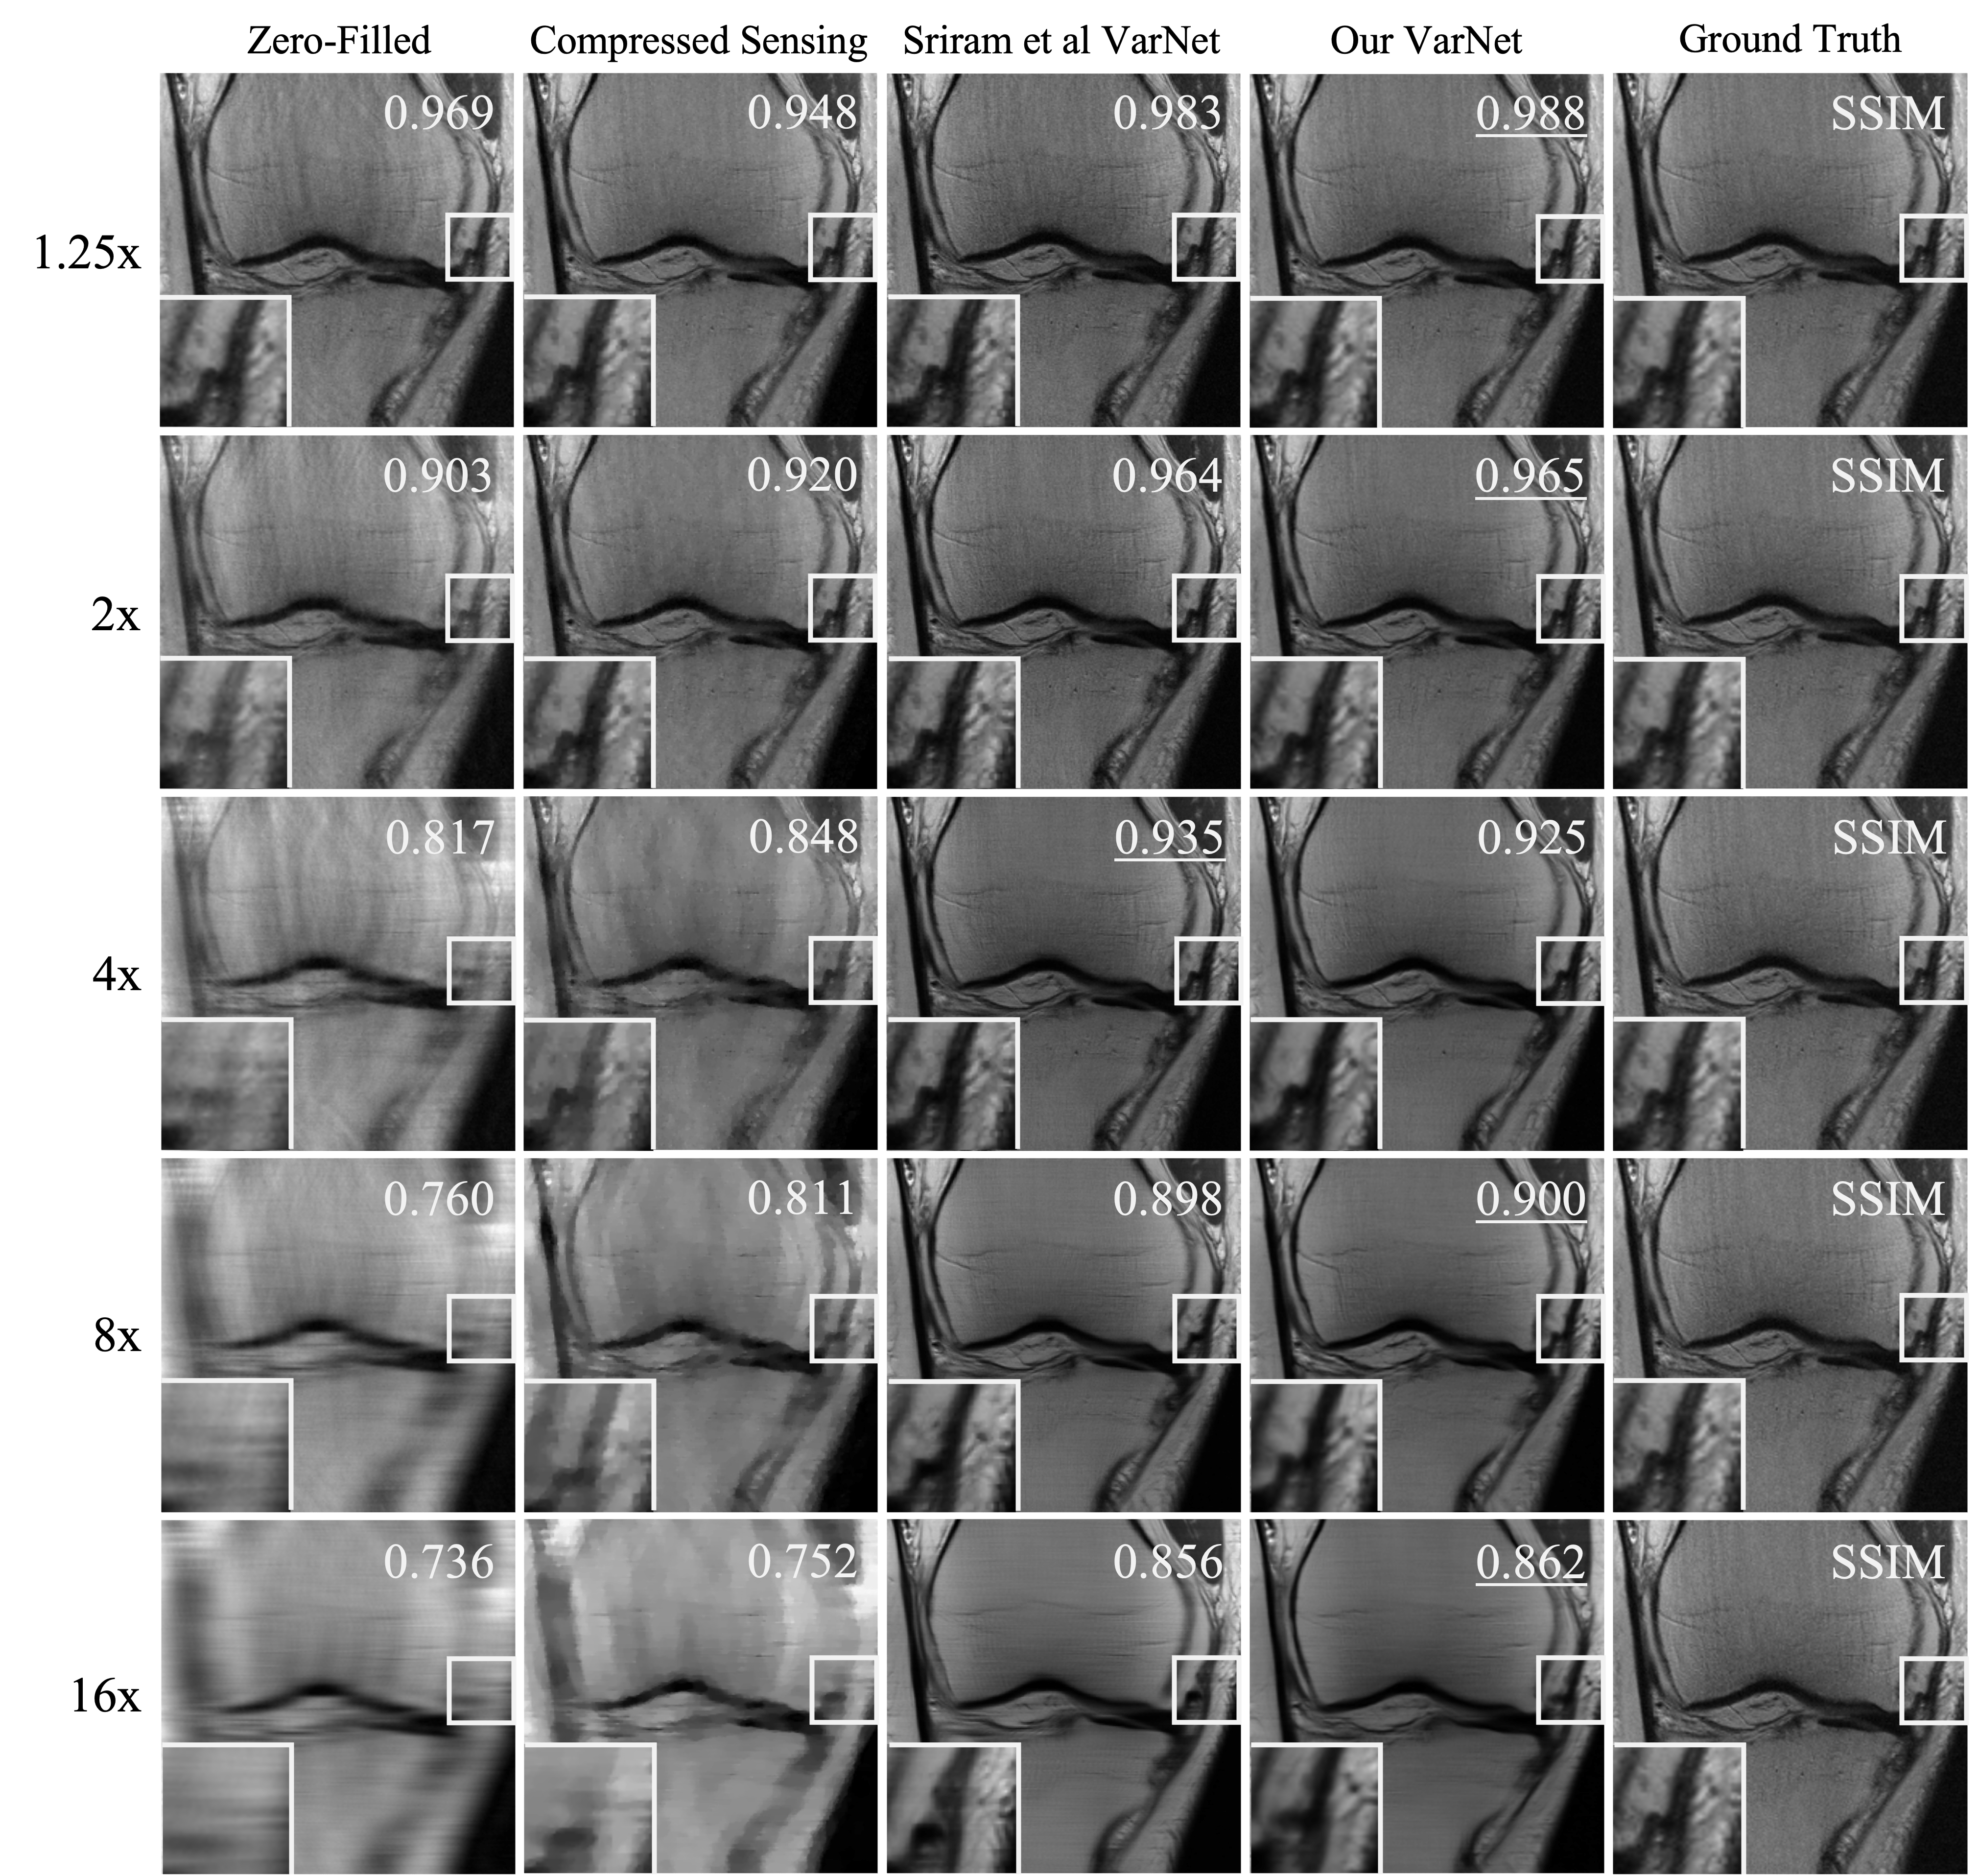

4.2 Acceleration Factor Balancing

Training our model on variably accelerated data improved its reconstructor performance on input data with acceleration factors that were either greater than 8x or less than 4x when compared to the original E2E-VarNet model (Sriram et al., 2020). However, we also noticed that our model performed comparable to Sriram et al’s original E2E-VarNet at 4x acceleration factor, and better than the original model at 8x acceleration factor (\tablereftable:reconstructor). This suggests that training accelerated MRI reconstruction models on variably accelerated data may offer improved performance at almost all stages of a clinical patient scan.

A.2 Acceleration Factor Balancing

To simulate variable acceleration factors, we randomly masked the slices in the fastMRI training by sampling the number of unmasked lines from a uniform distribution , where and width is the number of Cartesian -space columns in the slice. The acceleration factor could then vary anywhere between approximately 20x to a fully sampled dataset. Because the acceleration factor is proportional to the inverse of the fraction of unmasked lines, the distribution of acceleration factors in our training dataset therefore followed an inverse power law. Training was conducted on the fastMRI multi-coil knee training dataset partition. The results reported in \tablereftable:reconstructor were generated from the fastMRI multi-coil knee validation dataset, which was withheld during training of our model.

B.2 Acceleration Factor Balancing

In \tablereftable:reconstructor-brain-supp, we report reconstructor results exploring the impact of training reconstructor models on variably accelerated undersampled brain datasets. We also provide sample image reconstruction panels from our experiments in \sectionrefsection:var-acceleration to illustrate conclusions drawn from our experiments. Images were reconstructed using knee (\figurereffig:reconstructor-knee) or brain (\figurereffig:reconstructor-brain) models that were both trained on variably accelerated data. Finally, we include a panel of histograms in \figurereffig:var-knee-histogram visualizing the distribution of pair-wise SSIM improvement in undersampled multi-coil knee reconstruction using a reconstructor trained on variably accelerated data when compared to one trained on only 4x and 8x accelerated data.